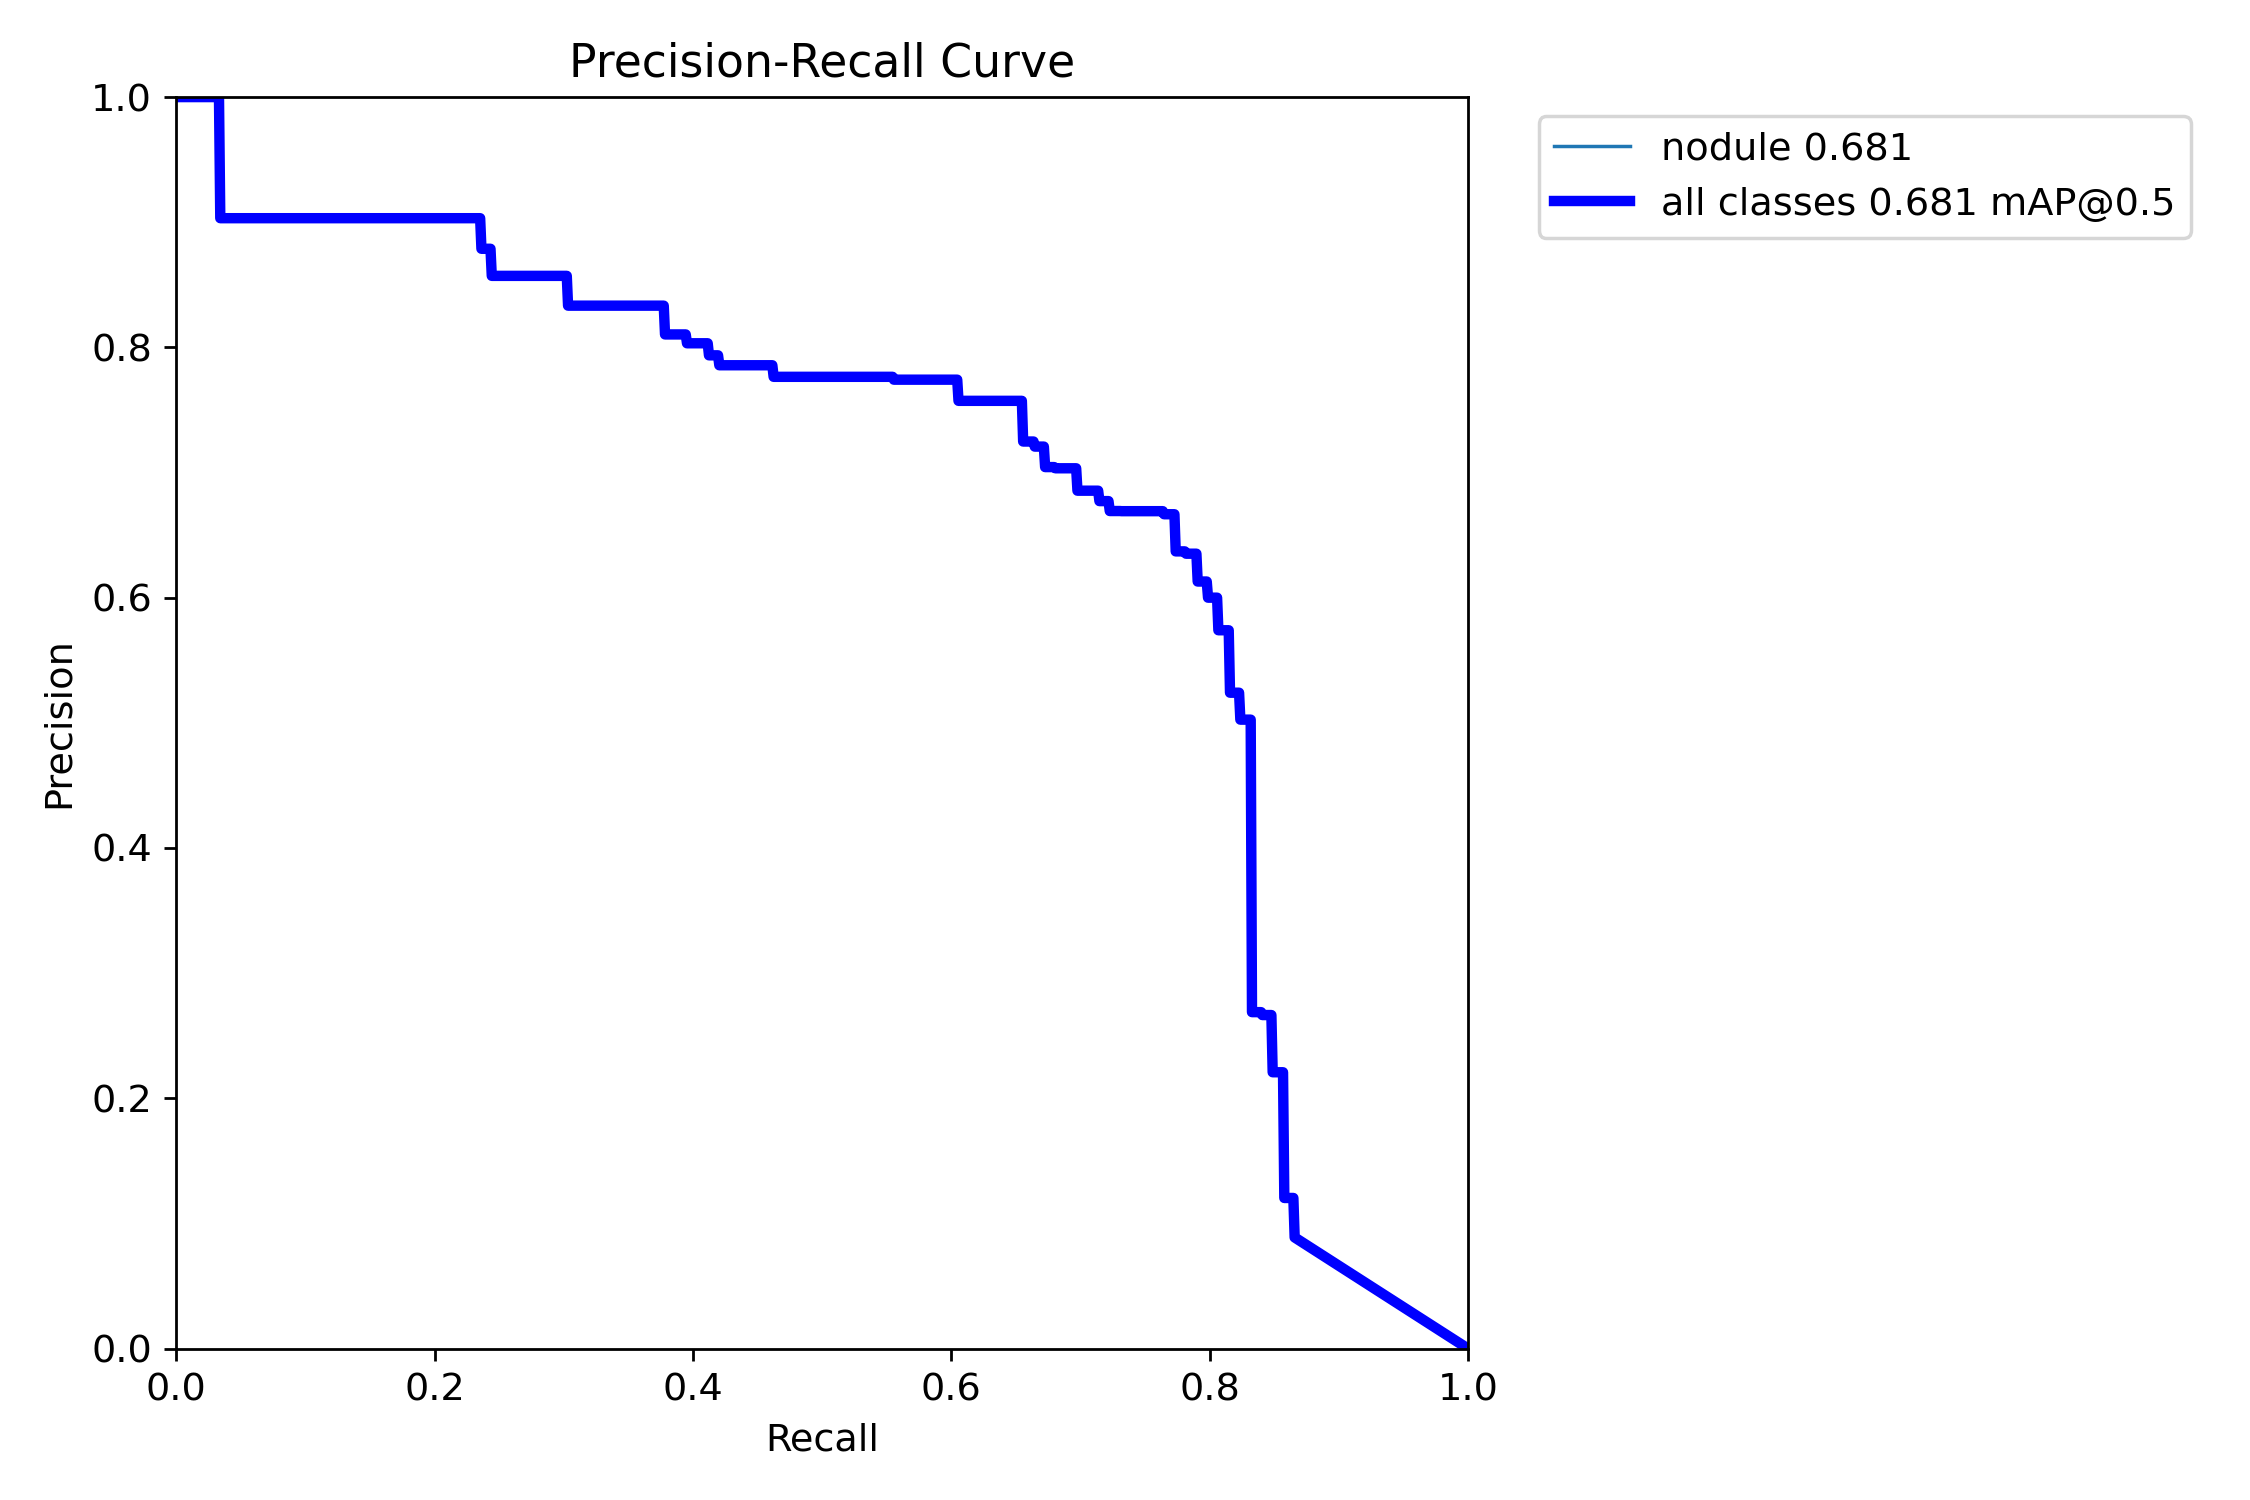

当iou阈值为0.5的时候,模型在测试集上的map可以达到68.1%。下面是一个预测图像,可以看出,我们的模型可以有效的预测出这些尺度比较小的交通目标。